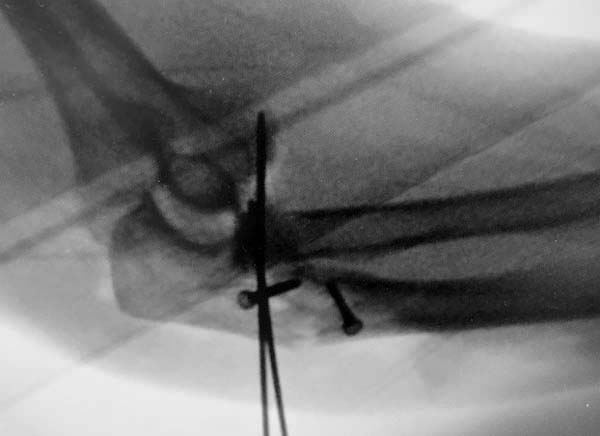

На локтевую кость - можно обойтись пластиной. На лучевую кость - стержневая фиксация т.е. обычные 2мм спицы, но с конверсивной геометрией.

Конверсионные спицы на уровне проксимального отдела лучевой кости интересная идея, но на уровне перелома в области шейки трудно удержать головку. Предварительная репозиция локтевого отростка с временной установкой пластины, затем удаление экономит время. Доступ через локтевой отросток, где можно фиксировать или удалить головку с замещением, а потом установить пластину обратно на локтевой отросток!